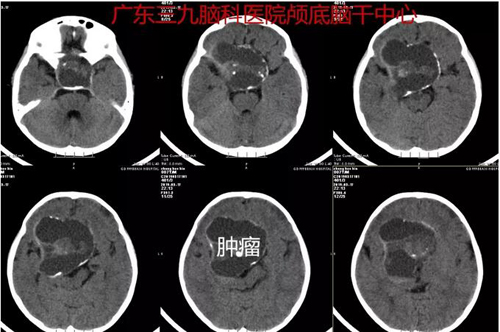

住院后,相关检查提示,鞍上-鞍上区(突破鞍隔至蝶窦)示团片高低混杂密度影,直径超过5厘米,邻近的脑实质受压,骨质破坏。考虑颅咽管瘤可能性大,因肿瘤压迫视神经,小宝的视力仅有光感。

图1:术前CT示鞍上-鞍上区(突破鞍隔至蝶窦)示团片高低混杂密度影,范围约59×54×55mm,周围示少许钙化影。邻近脑实质受压,邻近骨质破坏。